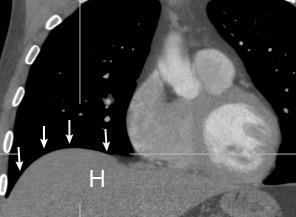

Diafragma “colgante” (“dangling sign”)

(“Dangling sign”)

TC. Mejor con multicorte. (reconstrucciones).

Asociación: Aire en pared.

Fracturas costal .Rotura esplénica. Neumoperitoneo.

Diafragma discontinúo Herniación de la grasa omental

Desser TS et al.The dangling diaphragm sign: sensitivity and comparison with existing CT signs of blunt traumatic diaphragmatic rupture. Emerg Radiol 2010